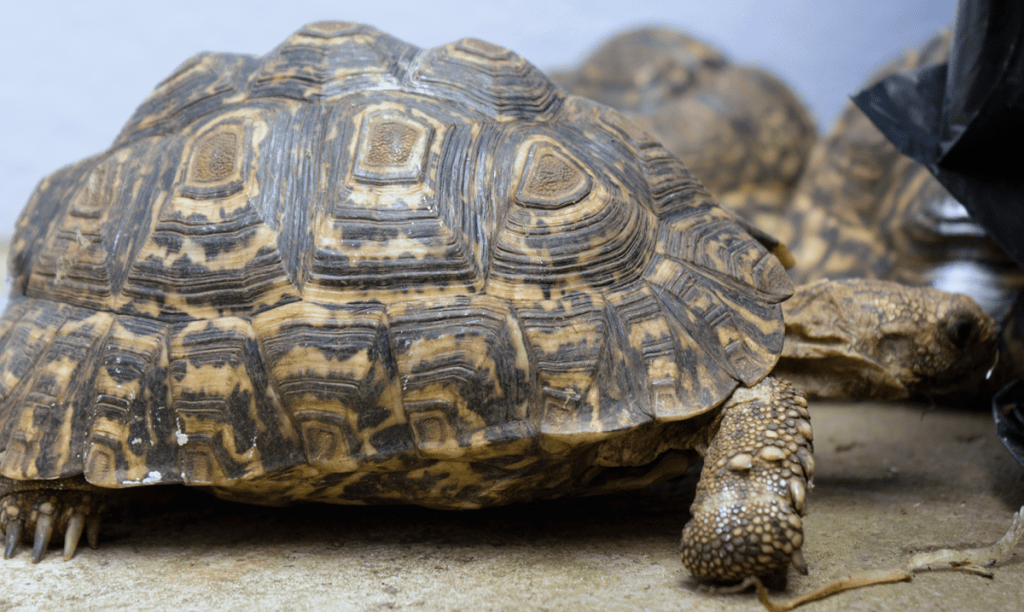

De nos nouveaux patients sont arrivés, de belles tortues léopards ! Hélas, elles ne mangent plus, il doit y avoir un problème.

De nos nouveaux patients sont arrivés, de belles tortues léopards ! Hélas, elles ne mangent plus, il doit y avoir un problème.